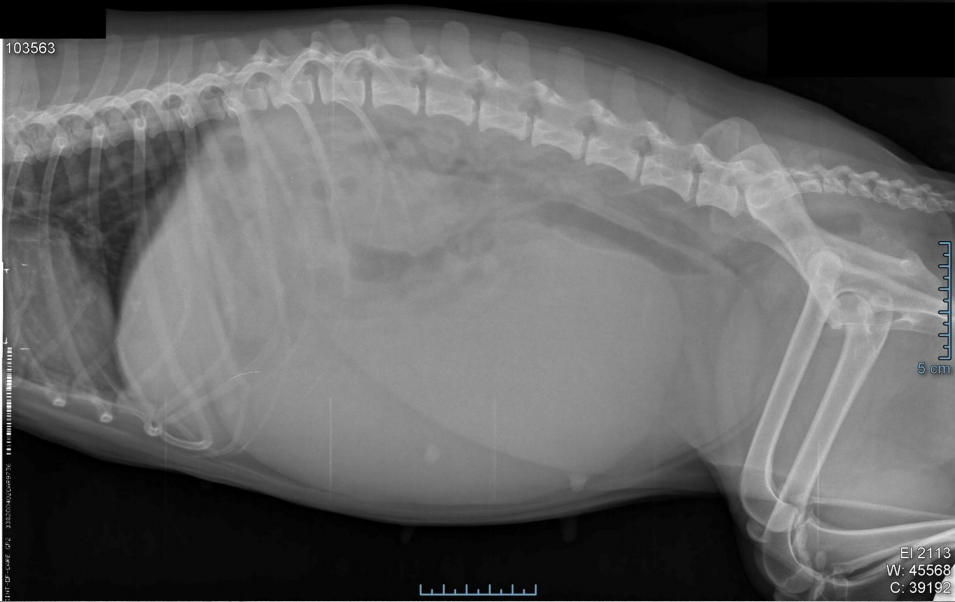

●13 yo male castrated cat

●Anorexia, lethargy

●Weight loss

● Decreased serosal details. Margins of

organs not visualized.

● Abdomen distended.

● Abdominal effusion (ascites).

● Due to Mesothelioma (cancer of the peritoneum and serosal surfaces)

Main 3 ddx for ascites.

heart disease

tumors

liver disease